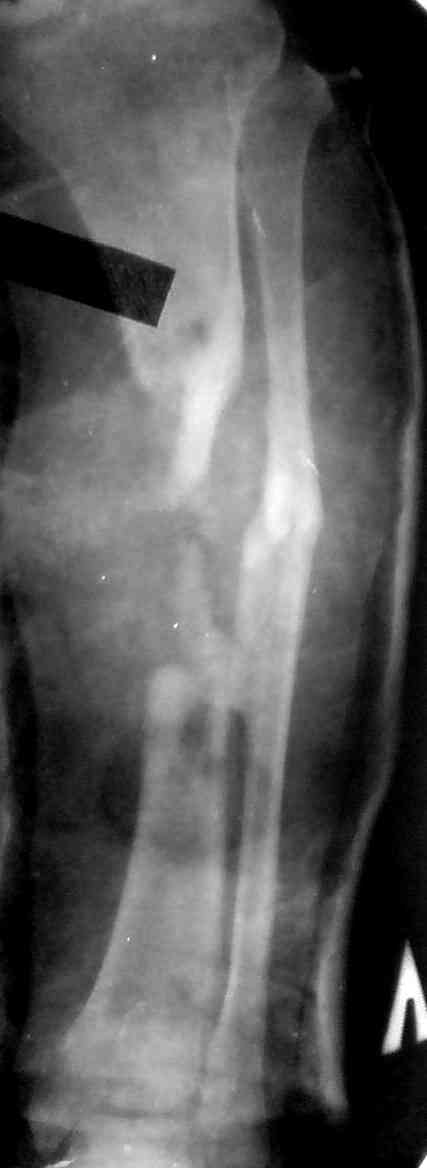

Кстати на предоперационных снимках видно, что Ваш пациент имел Сегментарный перелом на границе верхней и средней трети большеберцовой кости и средней трети большеберцовой кости. Непонятно почему был удалён средний сегмент перелома.Почему в течении такого большого времени не предпринимались попытки для замещения деффекта.

Судя по месту расположения свища, наличия литического учаска в проксимальной части дистального фрагмента на последнем снимке, и, наличие в этом месте стержня Шанца на послеоперацционном снимке, причина остеомиелита у Вашего пациента спицевая.